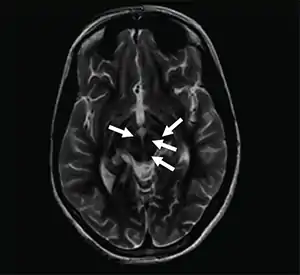

The face of the giant panda sign, panda sign of the midbrain or double-panda sign is a characteristic "panda's face" appearance in magnetic resonance imaging (MRI) images of people with Wilson's disease. Along with Kayser–Fleischer rings, the sign is helpful in diagnosis.[1]

| Axial T2-weighted MRI of the brain at the level of the midbrain showing the characteristic ‘face of the giant panda’ sign, with normal red nuclei and substantia nigra (pars reticulata) against a background of hyperintensity in the tegmentum, as well as hypointensity of the superior colliculi | |